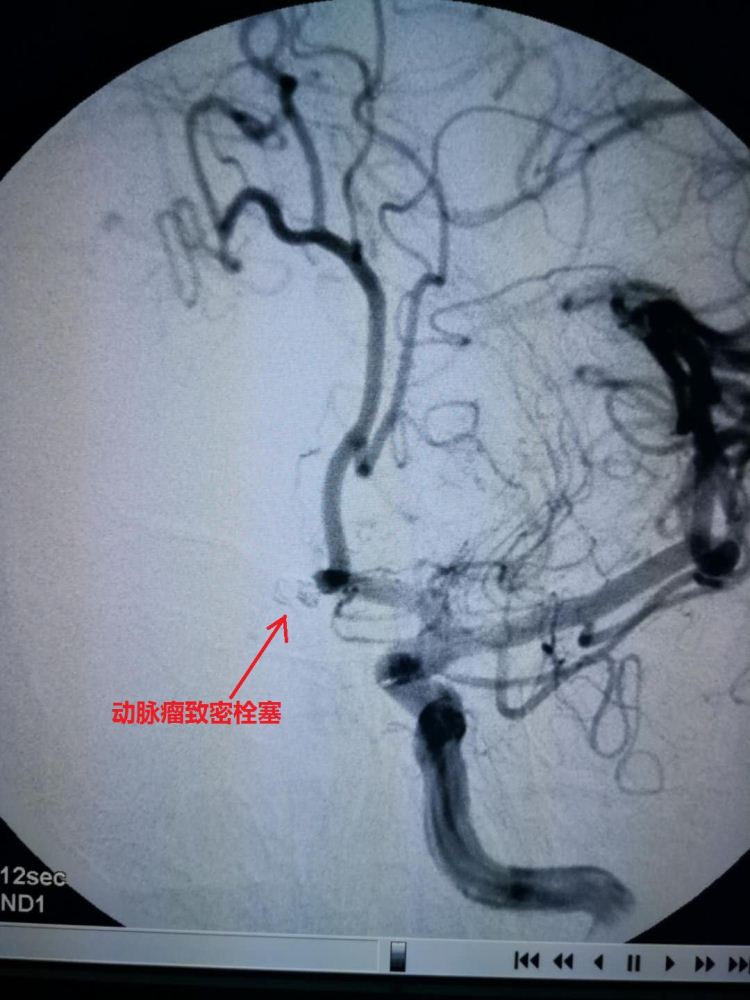

脑外科成功栓塞一例脑动脉瘤

2019年3月22日一早,太平的刘先生刷牙时突然出现剧烈头痛,伴随恶心呕吐,拔打“120”来我院,通过“脑卒中”绿色通道,30分钟内完善颅脑CT、心电图及术前抽血检验,诊断为“蛛网膜下腔出血;颅内动脉瘤可能性大”,给予应用控制血压、止血药等稳定病情后,60分钟内完善颅脑CT血管成像检查,明确诊断为“前交通动脉瘤”。我院脑外科张新军副主任医师应用山东省医学影像研究所济阳区中医医院工作站,与省级专家共同讨论介入栓塞微创治疗脑动脉瘤的可行性后,赵建营主治医师又邀请山东省立医院神经外科教授协助手术。下午16:30手术开始,仅用35分钟的时间完成了前交通动脉瘤的完美栓塞和右侧脑室穿刺引流手术。术后第二天,患者头痛症状明显缓解;术后第五天,基本无头痛症状,拔除头部引流管,目前,该患者正在康复中。

脑外科脑动脉瘤的成功栓塞,让微创治疗技术更加成熟,为更好的服务百姓奠定了基础!同时也标志着我院“脑卒中”绿色通道已运行成熟。山东省医学影像研究所济阳区中医医院工作站的启用,也为我区百姓在家门口就能享受省级专家的诊治提供了有力保障!

术后效果